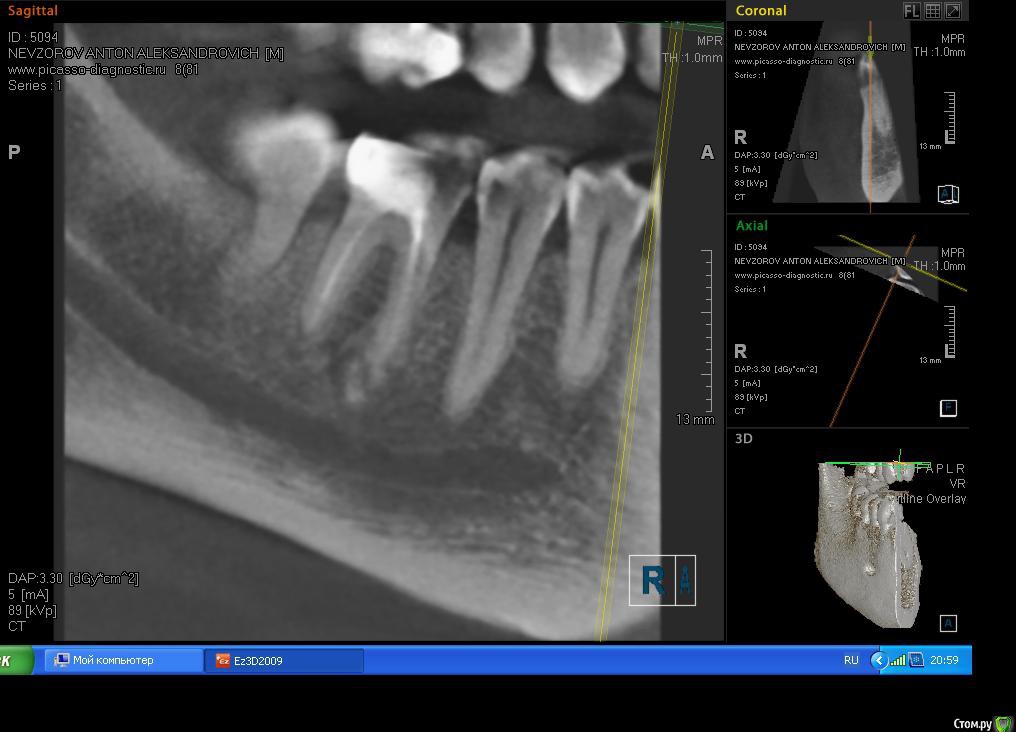

Antonbet Опубликовано 30 апреля, 2015 Поделиться Опубликовано 30 апреля, 2015 Подскажите,мнение врачей разделилисьОбнаружилась киста на 6 зубескажите что делать пролечивать каналы заново(4-5 мес.за 10 000 руб.) затем ставить коронку (15000 руб.) или удалять зуб и ставить имплант с коронкой (30 000 руб.),пр-во Израильесли имплант то можно ли ставить израиль ? или только швейцарию,Сша,они в 2 раза дорожеспасибо Ссылка на комментарий

Чертков Александр Опубликовано 30 апреля, 2015 Поделиться Опубликовано 30 апреля, 2015 Я за "перелечить". Судя по данным томограммы - вполне "жизнеспособный" зуб. План разумный. Ссылка на комментарий

Yana guapa Опубликовано 30 апреля, 2015 Поделиться Опубликовано 30 апреля, 2015 Подскажите,мнение врачей разделилисьОбнаружилась киста на 6 зубескажите что делать пролечивать каналы заново(4-5 мес.за 10 000 руб.) затем ставить коронку (15000 руб.) или удалять зуб и ставить имплант с коронкой (30 000 руб.),пр-во Израильесли имплант то можно ли ставить израиль ? или только швейцарию,Сша,они в 2 раза дороже спасибоImage.jpgImage1.jpg и первый и второй вариант лечения имеет право быть. Для первого варианта надо найти хорошего терапевта, желательно работающего с микроскопом. Но гарантий после перелечивания , конечно, немного все равно. Ну а по стоимости даже по нашим провинциальным меркам это ооочень не дорого, хорошее перелечивание каналов с микроскопом стоит дороже, да и импланты сейчас подросли в цене. Ссылка на комментарий